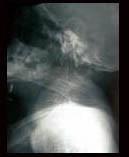

问题 某女46岁,颈项部疼痛1年,双上肢麻木无力8个月。查体有颈部运动受限,腱反射减弱。颅颈侧位片如图示,本病最可能诊断为 ( )

选项 A、颈椎病 B、椎管内肿瘤 C、扁平颅底 D、颅底凹陷症 E、小脑扁桃体下疝畸形 一、单项选择题

答案 D